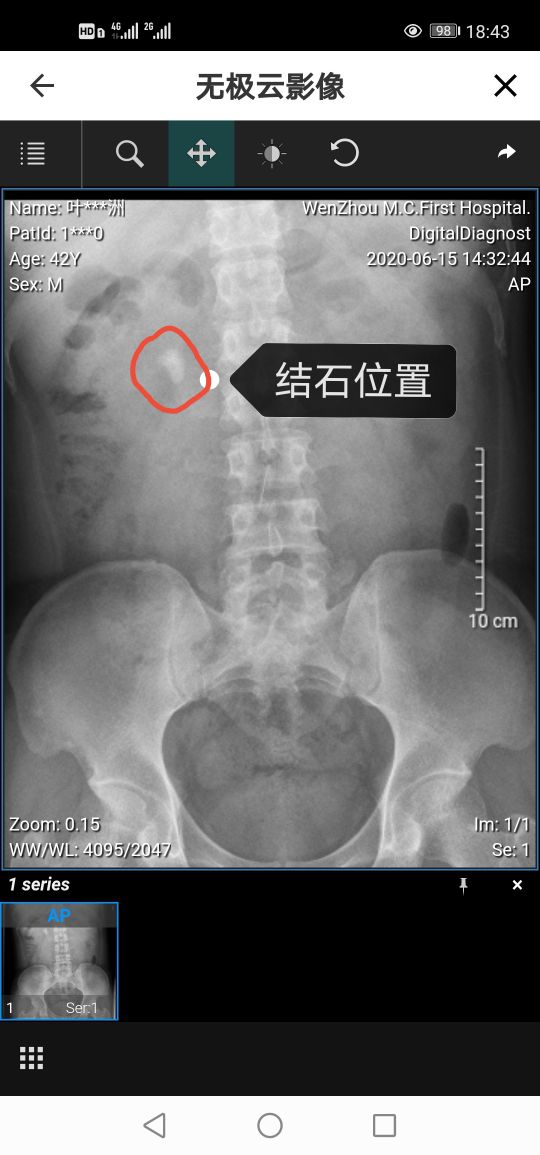

6月初因头晕心慌,去医院做检查,拍了CT。结果心脑系统没事,倒是意外发现右侧肾输尿管处有一枚结石,宽度1.5公分,长度3公分,刚好卡在右肾输尿管口处,而且肾部已经有少量积液。之所以说比较意外是因为肾结石一般会有痛感,血尿等症状,而我却一直没有感觉。后来才知道痛不痛跟结石存在的位置有关系,如果结石在肾部,因为肾脏本身无痛感神经,所以就不会疼痛。但是如果在输尿管的话只要和管壁摩擦就会出现痛感并且出现不同程度的血尿。这次检查虽然发现了肾部结石,但是自我感觉终归自己还算幸运的,琢磨着这病情没有出现恶化时就被发现,算起来应该也是省去了不少痛苦少花了不少钱吧,也不枉老妈平时那么虔诚的信佛,往功德箱捐了不少钱。

第二天,坐在轮椅上被人推着去拍了片子。从片子里可以清楚的看到一根双J管通过输尿管连着肾脏和膀胱。其作用就是支撑输尿管,防止血液或者残余结石堵塞输尿管,起到了一个疏通的作用。并且,肾部也看不到任何结石的残留,说明手术还是成功的。